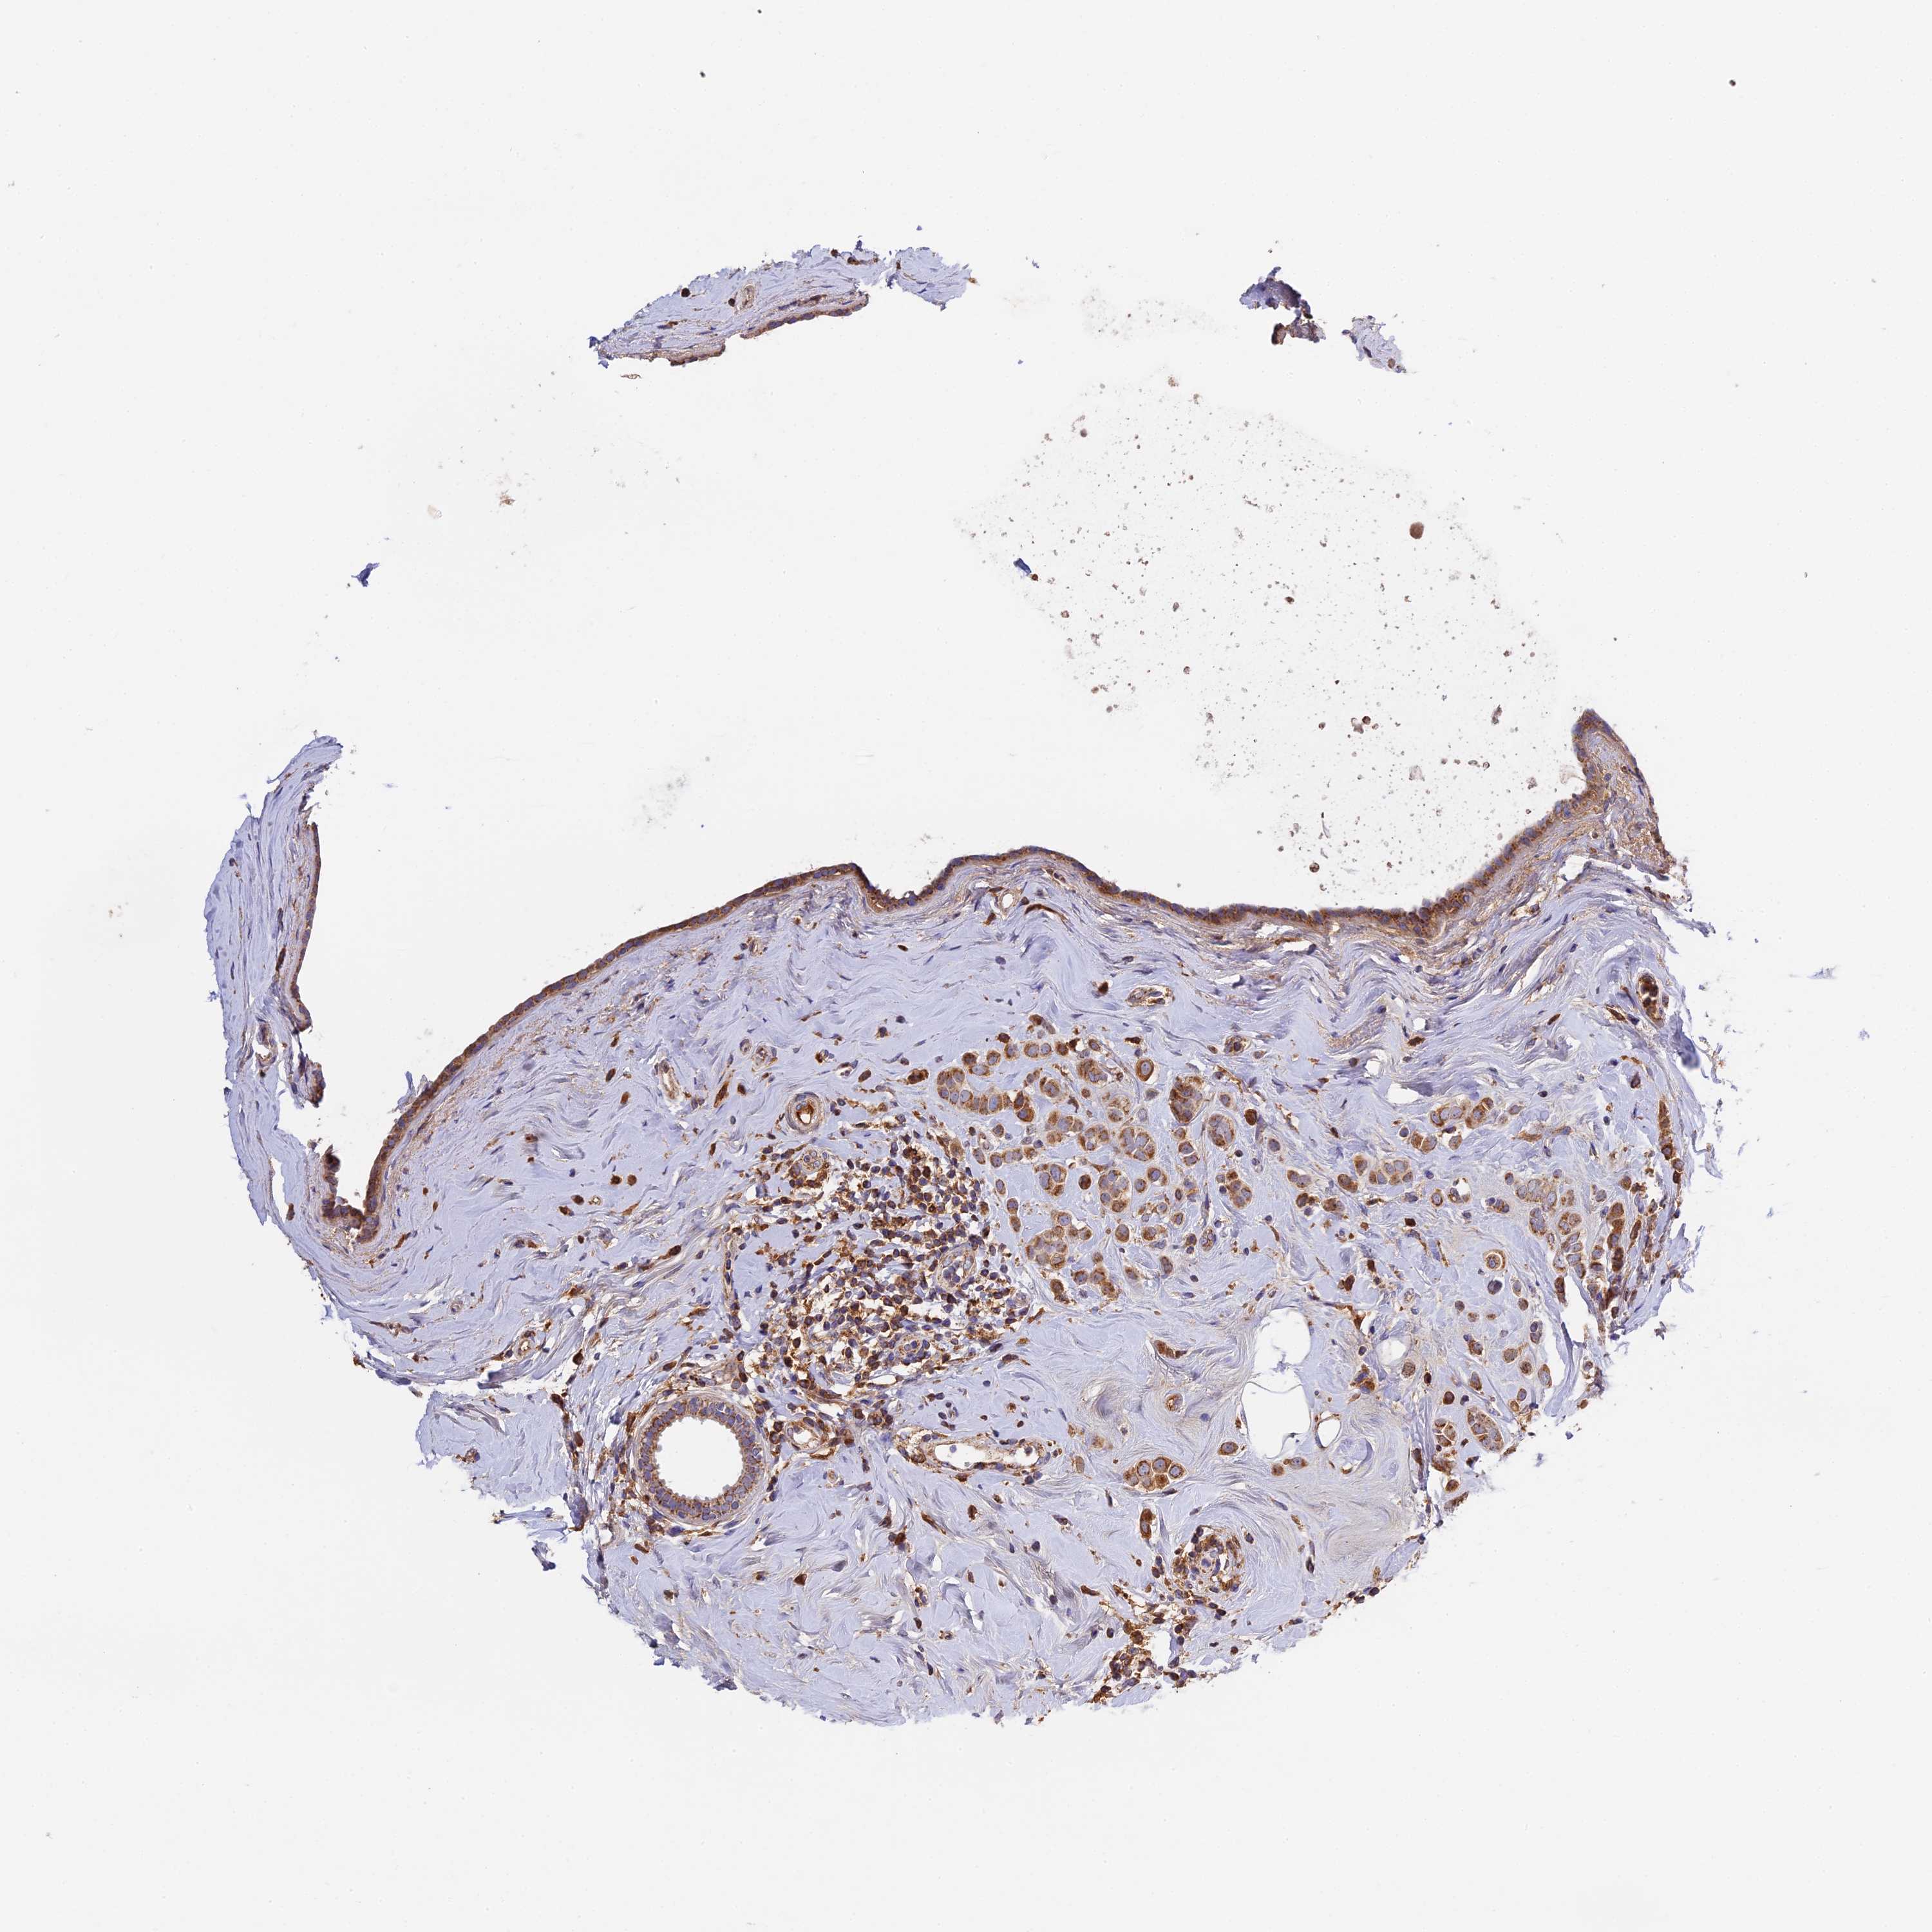

CANCER BREAST CANCER Show tissue menu

BRCA TCGA BRCA VALIDATION PROTEIN EXPRESSION